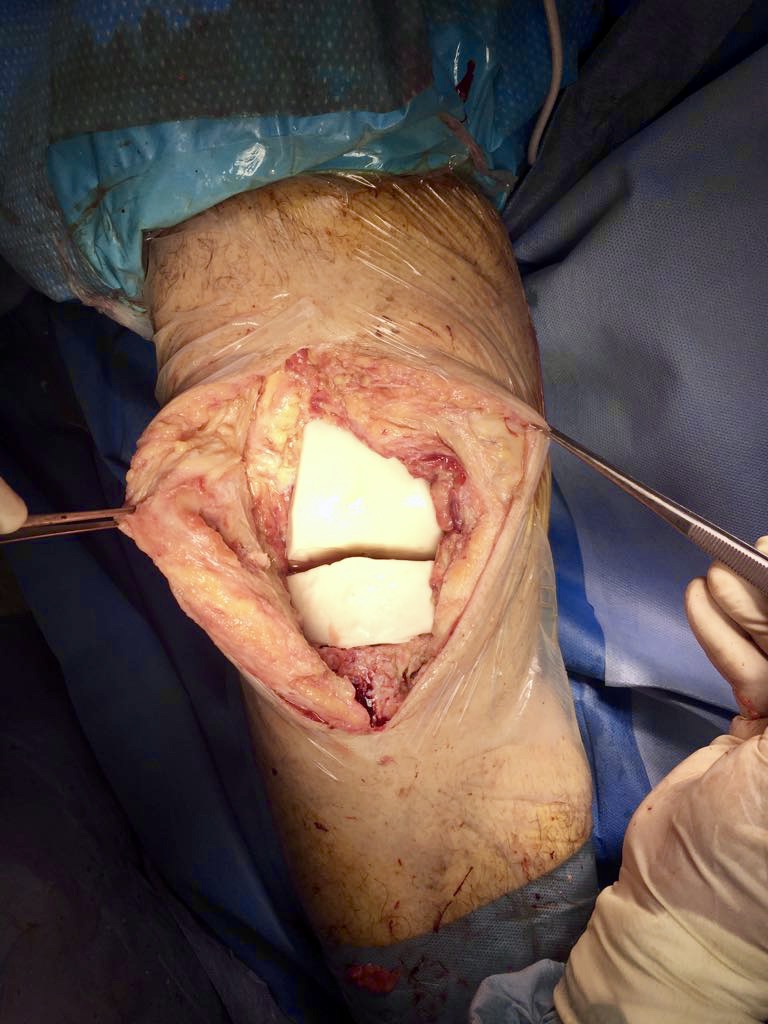

- Il ginocchio di Giuseppe, ormai nostro Amico : operato al Nord , si infetta . Tutti lo rifiutano. Nessuno lo vuole accogliere. Il Nostro Reparto , il Nostro Ospedale , SI! Una storia……per fortuna a lieto fine.